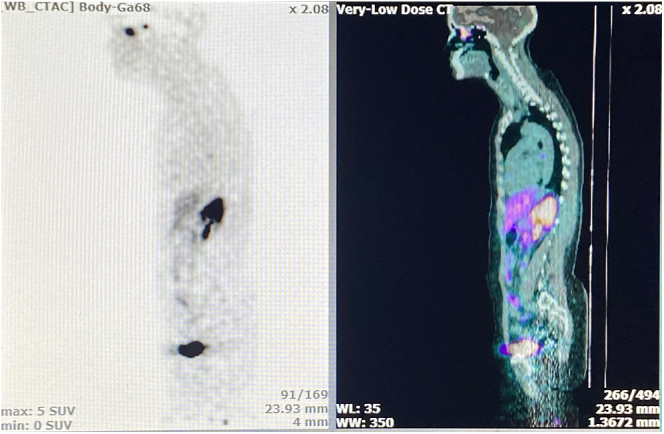

Case presentation: We describe a 42-year-old woman with a 4-year history of cyclical, symptomatic hyponatraemia characterised by intermittent episodes of dizziness, severe headaches and marked fatigue, initially without overt nasal or otolaryngological symptoms. Investigations confirmed SIADH, yet repeated imaging (including thoracic CT and FDG PET-CT) failed to identify a source. Eventually, a 68Ga-DOTANOC PET-CT revealed an isolated lesion in the left ethmoid region. Surgical resection via an endoscopic approach confirmed the diagnosis of a Hyams grade 1 ONB. Following complete tumour removal, the patient's hyponatraemia resolved.

Conclusion: This case highlights the importance of considering ONB in patients with unexplained SIADH, especially when initial investigations are inconclusive. It also underscores the utility of 68Ga-DOTANOC PET-CT in detecting occult neuroendocrine tumours, and reinforces the value of prompt surgical intervention for definitive treatment.